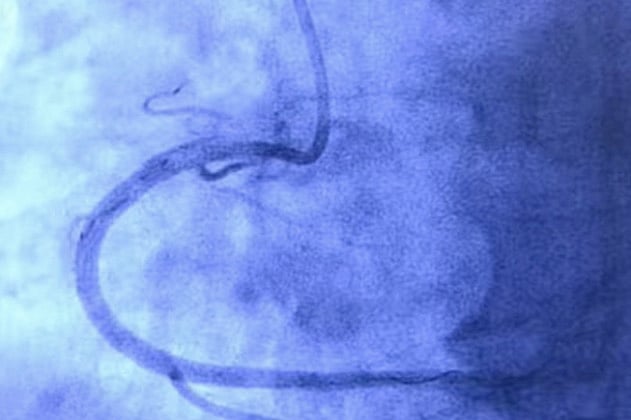

The technique is called Percutaneous Coronary Intervention (PCI), where the cardiologist will make a small opening in the hand of the patient, and insert a catheter (wires and tubes) into the a primary artery, and will approach the blocks near the heart. Once there, the doctor will blow a balloon up to push the blocks away and out of the path of the blood flow. Once Dr. YVC is satisfied that the heart is beating normally and blood flow is perfect, he will remove the catheter, and close the opening in the hand. This form of angioplasty - called the Trans Radial Angioplasty - was pioneered in India by Dr. YVC

In certain cases, the doctor may also implant a stent which holds the artery wall up, pushes the plaque against the wall, and ensures blood flow is free.

A bifurcation stenosis is when the blocks - stenosis - is situated at a point where the artery branches into two - and it is extremely important to remove both blocks at the same time.

Dr. YVC performs a similar PCI procedure  for Bifurcation angioplasty, in which special techniques are used to clear the blocks in both the main vessel and the branch. He is one of the pioneers in primary angioplasty, having performed the first procedure in 1995. He also has performed the most number of such procedures - across the country and perhaps the world. High volumes, in the doctor’s case - means that his expertise and his experience allows him to give more and more patients the most effective cure, with the least possible pain. Practice, indeed, does make perfect.